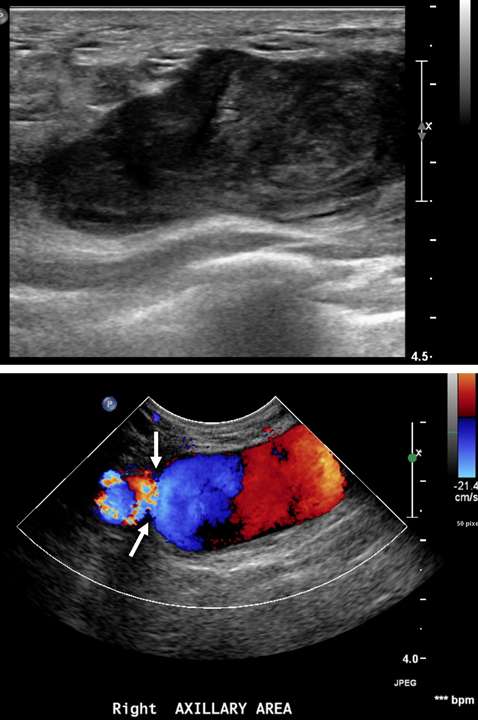

False aneurysm, or pseudoaneurysm, of the breast may be post-traumatic (blunt or penetrating), iatrogenic (e.g., post-biopsy, post-surgery), spontaneous (secondary to hemorrhage in the setting of coagulopathies or uncontrolled hypertension), or from vascular invasion by breast malignancy. The diagnosis of a breast pseudoaneurysm, if superficial, can often be made clinically by the presence of an expanding palpable, pulsatile mass on physcial exam. However, Doppler ultrasonography is the gold standard for confirming the diagnosis and characterizing the lesion for subsequent treatment planning (Figure 5). In the setting of acute trauma, breast and axillary pseudoaneurysms are usually identified radiographically during a trauma CT scan. Prompt treatment of pseudoaneurysms, especially if enlarging, is recommended in order to prevent clinically significant hemorrhage and rupture. The choice of therapy is guided by both clinical factors and imaging features, but generally involves an initial trial of manual external compression. This can be performed using an ultrasound probe, which allows the clinician to monitor treatment progress under real time visualization. More invasive intervention is warranted if there is persistent filling of the pseudoaneurysm sac, usually done in a step-wise fashion of increasing invasiveness. The first-line therapy is ultrasound-guided direct thrombin injection, which is only performed for pseudoaneurysms with features of a narrow (and preferably long) communication to the native artery origin (i.e., narrow "neck"). Thrombin injection is performed by slowly injecting a small volume of concentrated thrombin solution via direct needle puncture under constant ultrasound visualization. The procedure is well tolerated, however, there is a risk of distal embolization/migration which can lead to arterial thrombosis and ischemia; thus, thrombin injection should only be performed for pseudoaneurysms with a confidently seen narrow neck. Second-line therapies include endovascular treatment and surgical repair. Endovascular treatment is accomplished either via transarterial embolization of the sac using vascular coils and/or liquid embolic material, or by deploying a covered arterial stent across the pseudoaneurysm, thereby excluding the sac from arterial inflow. The latter is less preferable, as it requires post-treatment anticoagulation to mitigate the risk of in-stent thrombosis and stenosis. Surgical repair is generally reserved for refractory pseudoaneurysms or those with unfavorable anatomy. The operation is performed by surgically ligating across the pseudoaneurysm supply and resecting or evacuating the sac hematoma.